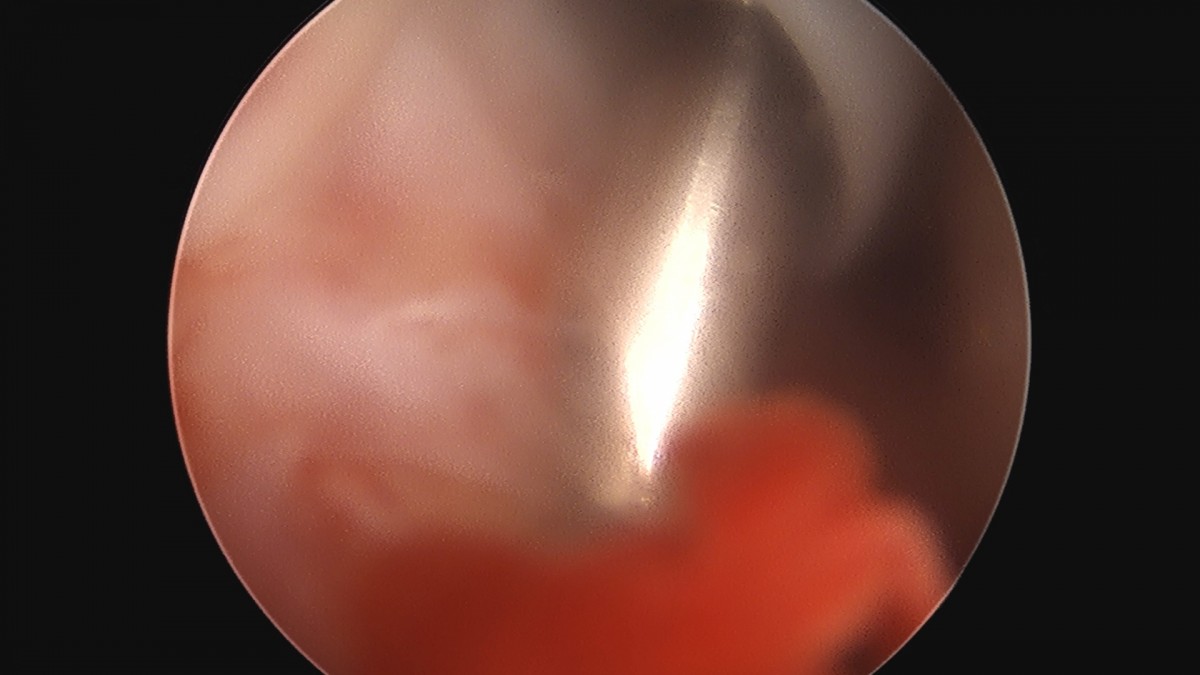

이재상원장님 어깨 견봉하 감압술 김선O 환자

dae765e4d9ac96aee867c9d6292d8784_1758004048_3083.jpg